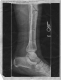

All in all, not a bad set of injuries for someone who just fell six stories. The surgery they had to perform on me is what gave me the wicked robot leg you can see in my profile picture. It's called an external fixator (mono-lateral for you sticklers out there) and it consisted of four 4-5 inch bolts drilled straight into my shin, with a connecting bar on the outside. Because my bones both broke through the skin, casting the leg wasn't an option. They didn't want to put a cast on it and then risk getting the healing flesh infected. Irony would prevail later on, but we'll talk about that when the time comes. I stayed in the hospital for 5 days ( I think) and then went home. I wasn't able to walk without a walker. Crutches were out, because of the healing chest tube wound under my left arm. Oh yeah! The chest tube! I had a tube between my ribs that helped get the fluid out of my lungs. Whenever I coughed, about a teaspoon of mucillagenous orange/yellow fluid would pour from my lung out the tube. It was sick. Moving on! I couldn't use crutches, so I walker'd and wheelchair'd places, but rested mostly.

I show up at orthopedics after calling for a same day appointment, and am introduced to Mark Okawachi, Physician Assisstant. Now I'm sure Mark meant well, and that he knows far more about medicine than me, but I was a little baffled when he told me that what I had coming out of my leg was in fact serous fluid, a benign clear-yellow liquid, and not pus. I informed him of my doctor's request to be seen that day, and he informed me that she was wrong. "Let's get x-rays first, to see if anything is wrong", he said. I got the x-rays, which Mark gave a shining review. "You're doing fine!" he said. "Let me just get one of our orthopedic surgeons to take a look at this." In comes Dr. Von Glinski, far less terrifying than she sounds, but with a very surgical, precise way about her. She takes one look at the x-rays, not even paying attention to my fracture and says to Mark "Look, there's erosion around the pin site. It's infected. We need to take the fixator out today, right now." Mark, foot firmly in mouth, looks at the x-ray and mumbles something to himself. Dr. Von Glinski looked at me just then, her piercing eyes seeming to size me up. She said, and I quote, "I bet those pins are treated with hydro(I couldn't catch the rest). *Looking away* That is gonna hurt like a son-of-a-bitch." Wide eyed, with a "Did I just hear my doctor fucking say that!?" stare, I turn to my Mom, who can't quite believe her ears either. At least she was frank about it.

The next day, Sunday, my brother is changing my wicking again, this time with my Dad looking over his shoulder. He finishes, and as I lift my leg to put it back in the boot, something funny happens: my leg bends. Not at any joint in particular, you see...in the middle of my shin, it bends. My brother and I exchange WTF glances, and my Dad and I decide it's time to book it to the ER. We get to Roseville ER, get in, get x-rays, and confirm the common sense fact: my leg is still really fucking broken. Roseville ER puts me in a non-removeable splint and tells me that this will get me through the weekend, but to get a cast on Monday.

But back to the leg...my full leg cast stayed on for 34 days, and did it's job well. My leg was immobile, but there was a slight problem. When I went in for x-rays on September 19th, my tibia looked like it hadn't been knitting at all. It was a possibility that because of the infection the healing would be delayed, but stopped altogether? Unlikely. My bone was exhibiting symptoms of nonunion, a permanent break. Bones don't always grow back together. It's not common in properly set and maintained fractures, but it does happen. On the 19th they decided to take my full leg cast off and put me in a patellar tendon cast, which lets me bend my knee but allows no torsion of the lower leg. To stimulate bone knitting, I got an ultrasound emitter that fits into a port on my cast above the fracture.